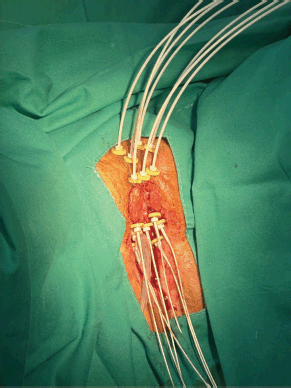

Under spinal anesthesia, the implant procedure involved placing three flexible catheters on each side of the urethra at different depths (roughly 1 cm between each), plus an additional superficial catheter in the central region of the tumour. The catheters were secured with small radiopaque fixation buttons (Figure 2). A post-implant CT scan was performed to confirm the positioning of the catheters relative to the GTV and OAR.

Figure 2. Case 1. The vulvar tumour and the implantation of seven interstitial catheters are observed.